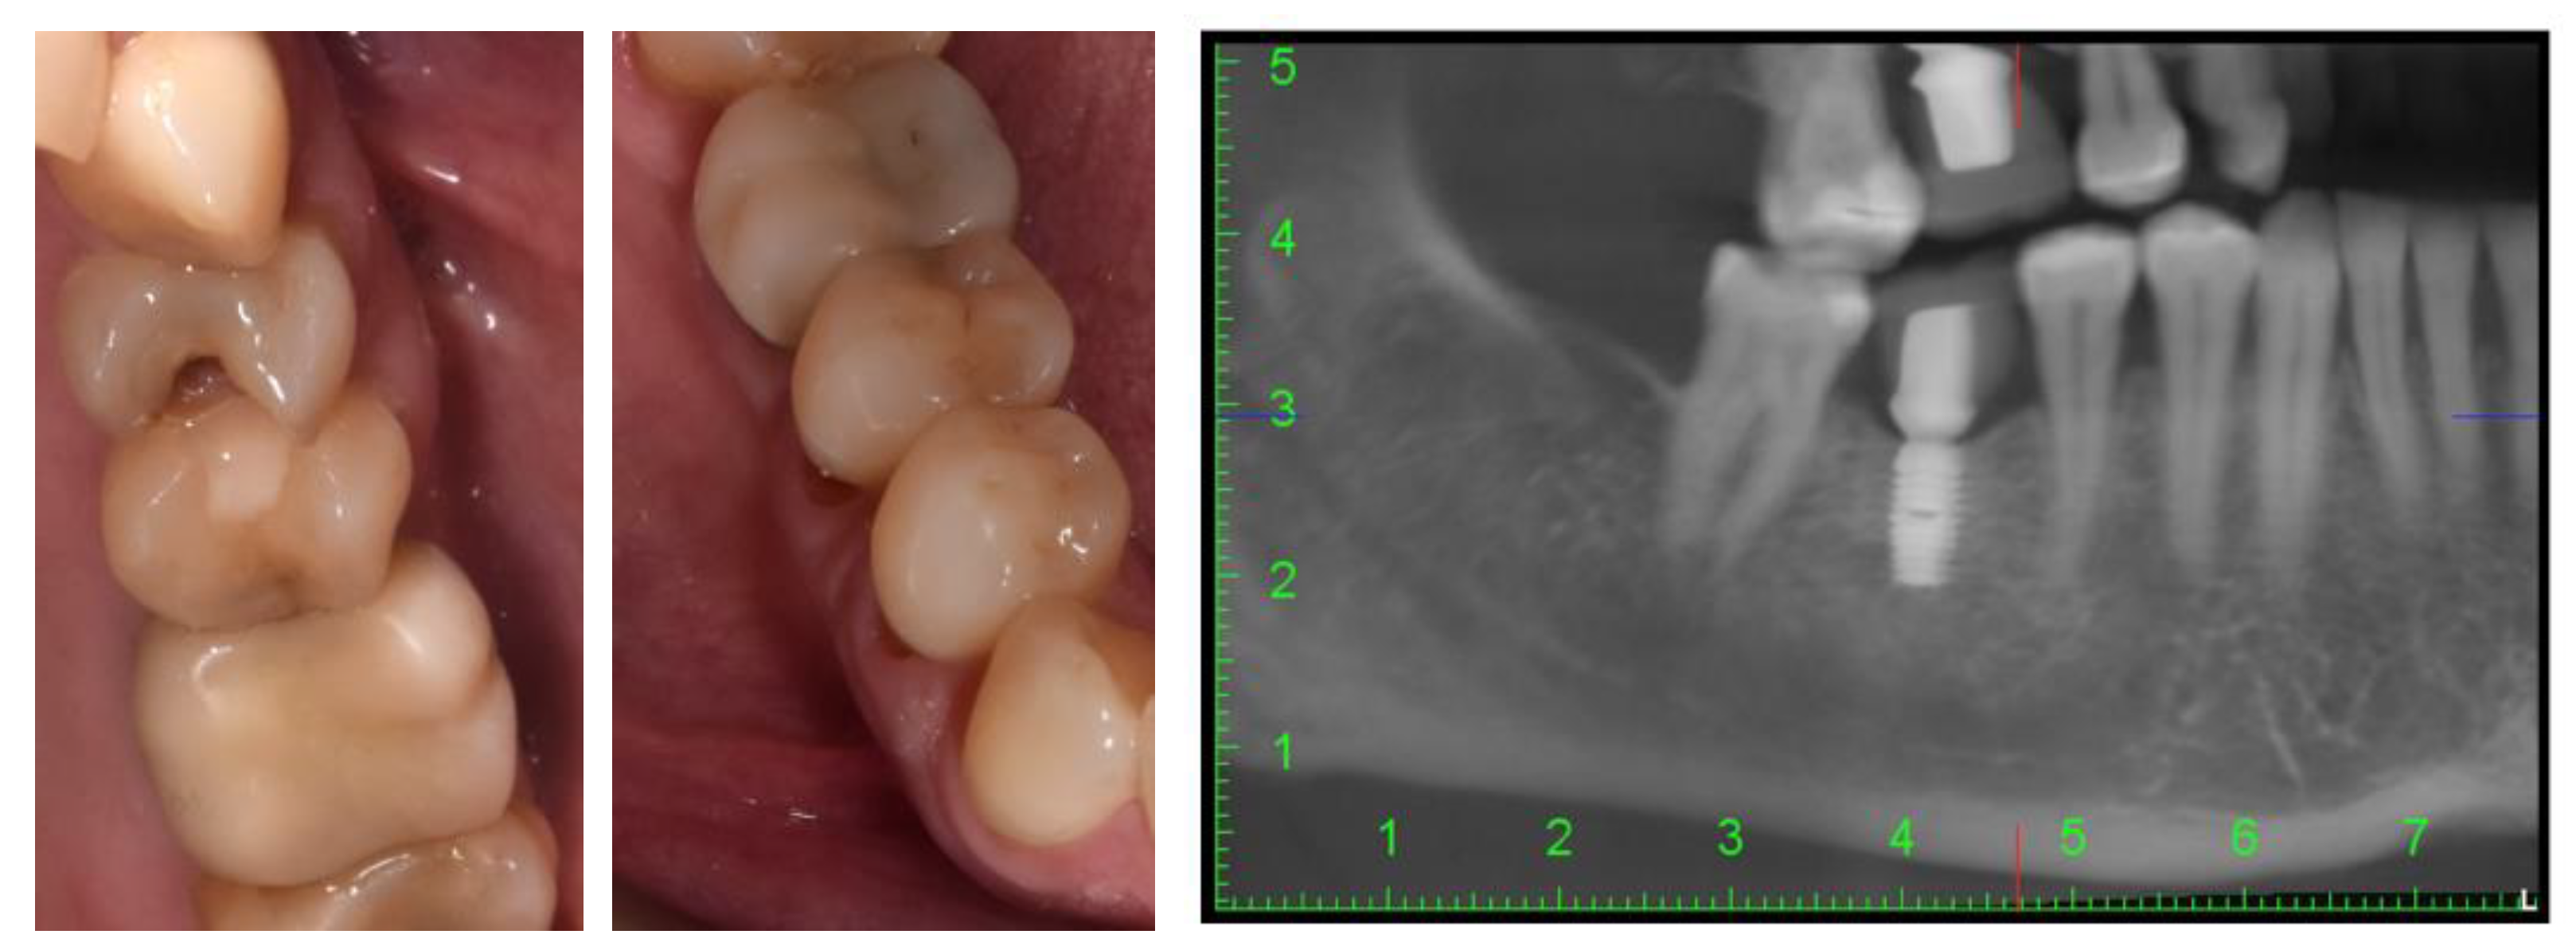

The intraoral examination revealed that the patient presented with multiple simple odontal lesions that were partially treated, correctly and incorrectly. A simple carious lesion affected the right upper first premolar (1.4) (Figure 1). Wear areas were also observed in the incisal and occlusal regions of the right lower canine and premolars, as well as abfractions, with exposed dentine, located in the buccal cervical zone of the mandibular right premolars. The aspect of abfractions was mixed-shaped (wedge and saucer), located in enamel and dentine, without prepared cavities, and without any bacterial deposits. The abfraction lesions were 1.2 mm in depth. The most commonly used index that categorizes tooth wear in the cervical region is the Tooth Wear Index by Smith and Knight [23]. The abfraction lesions of the lower right premolars were determined to be 3rd class (defects ranging from 1 to 2 mm deep).

Figure 1.

Intraoral aspects and CBCT image of patient.

The cervical margin of the patient’s abfraction lesions were located at the level of the free gingival margin. No gingival recessions were detected at the level of the cervical area of the two premolars. During the anamnesis and the clinical examination of the patient as well as later during the treatment and monitoring, no changes of periodontal tissues were detected (e.g., inflammation, gingival bleeding, the apparition of periodontal pockets, or dental mobility).

These mandibular right premolars presented with painful tooth sensitivity. The teeth appeal revealed the absence of 1.8, 1.6, 2.6, 3.5, 3.6, 4.6, and 4.8 teeth (after the FDI two-digit notation system). Cone-beam computed tomography (CBCT) of the orofacial area was indicated as a complementary examination. The patient’s missing teeth were already prosthodontically rehabilitated when she came to the dentist, through dental implants. She told us that these were short Bicon dental implants (facts confirmed by analysis of the CBCT images) with the superstructure made of hybrid ceramics.